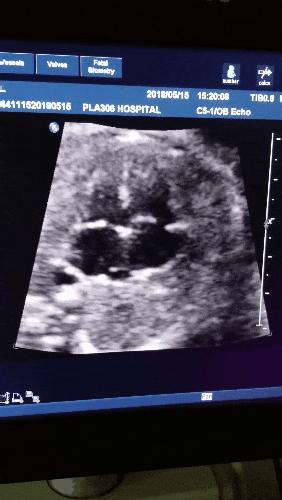

四、头臀长(Crown-Rump Length CRL)

“头臀长”一词是从20世纪早期胚胎学家那里借用来的,他们发现保存下来的早期流产标本是采取“坐在椅子上”的姿势,于是用头尾长度(冠部臀部长度)作为测量胎儿的一种可重复的方法。

CRL测量的是胚胎顶部和臀部之间的距离。

在妊娠6到12周之间测量CRL,是估计妊娠时间的最准确方法:

妊娠周数=CRL(cm)+6.5

注意:妊娠囊、胎芽长度、头臀长都可以用来推算孕周,但最准确的是头臀长。如果CRL未超过84mm时,应该用CRL来推算孕周,如果CRL超过84mm时,应使用头围来推算孕周。